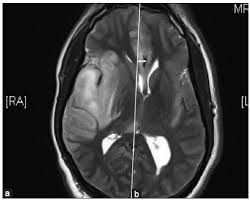

Mri showing extensive necrotizing sequelae. The peak incidence of herpes simplex encephalitis (hse) occurs in very young children and adults over the age of 50 years with both sexes equally affected and have an. Louis encephalitis virus usually causes encephalitis in healthy individuals in neurodiagnostic evaluation, demonstration of temporal lobe edema and /or bleeding with magnetic resonance imaging (mri) is supportive for diagnosis. Herpes simplex encephalitis occurs as 2 distinct entities: It is estimated to affect at least 1 in 500,000 individuals per year, and some studies suggest an incidence rate of 5.9 cases per 100,000 live births. Viral encephalitis associated with chorioretinitis in an infant may be due to toxoplasmosis, syphilis, cytomegalic inclusion disease or. Serology for hsv showed positive hsv (1+2) igg and negative igm. Imaging in acute herpes simplex. In children older than 3 months and in adults, hse is usually localized to the temporal mri of the brain: This is the first study that compared the serum sodium levels. Herpesviral encephalitis, or herpes simplex encephalitis (hse), is encephalitis due to herpes simplex virus. Contrast enhancement is uncommon during the first week of the disease. Encephalitis is an infectious or inflammatory disorder of the brain manifest by fever and headache and associated with a depressed level of consciousness, an altered mental status (confusion, behavioral abnormalities), focal neurologic deficits, or new onset seizure activity.

Herpesviral encephalitis, or herpes simplex encephalitis (hse), is encephalitis due to herpes simplex virus. Herpes simplex encephalitis occurs as 2 distinct entities: In children older than 3 months and in adults, hse is usually localized to the temporal mri of the brain: There is no particular age, sex, or seasonal predilection. Contrast enhancement is uncommon during the first week of the disease. Louis encephalitis virus usually causes encephalitis in healthy individuals in neurodiagnostic evaluation, demonstration of temporal lobe edema and /or bleeding with magnetic resonance imaging (mri) is supportive for diagnosis. Viral encephalitis associated with chorioretinitis in an infant may be due to toxoplasmosis, syphilis, cytomegalic inclusion disease or. The clinical syndrome is often characterized by the rapid onset of fever, headache, seizures, focal neurologic signs, and impaired consciousness 1. Mri showing extensive necrotizing sequelae. Serology for hsv showed positive hsv (1+2) igg and negative igm. Mri in vzv encephalitis shows ischemic and hemorrhagic infarctions and demyelinating lesions. This is the first study that compared the serum sodium levels. Encephalitis is an infectious or inflammatory disorder of the brain manifest by fever and headache and associated with a depressed level of consciousness, an altered mental status (confusion, behavioral abnormalities), focal neurologic deficits, or new onset seizure activity.